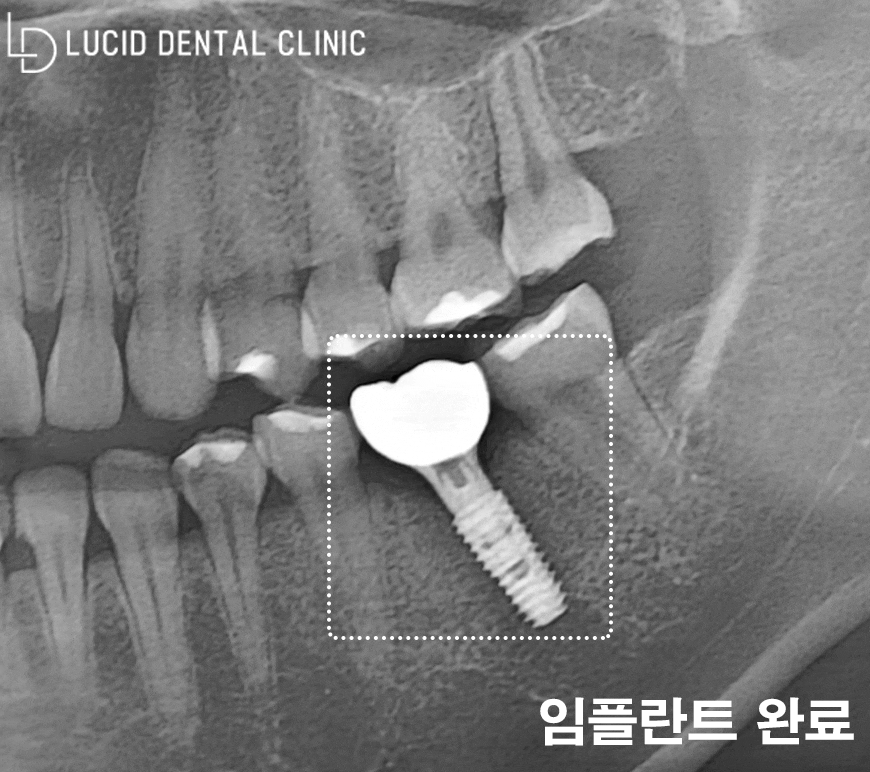

위와 같은 치료 과정을 거치며

약 3개월의 회복 시간을 보냈는데요

실제로 환자께서 정기 검진도 꾸준히 받아주시고,

관리도 꼼꼼히 시행해 주셔서 굉장히 빠른 속도로

회복하는 모습을 확인할 수 있었습니다.

이렇게 제작한 최종 보철을 체결해 드리며

계획한 치료 과정을 모두 마칠 수 있었습니다.